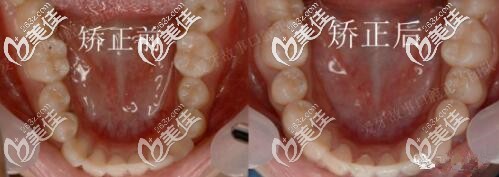

圖四前后牙弓對(duì)比

圖五下前牙對(duì)比

矯正用了1年半,地包天明顯改善,牙弓也擴(kuò)開(kāi)了。正畸期間口腔護(hù)理很重要,如果出現(xiàn)了口腔有異味或炎癥,就要隔兩到三天使用牙套清潔片把牙套泡一泡,必要時(shí)可用酒精棉片對(duì)牙套進(jìn)行消毒。